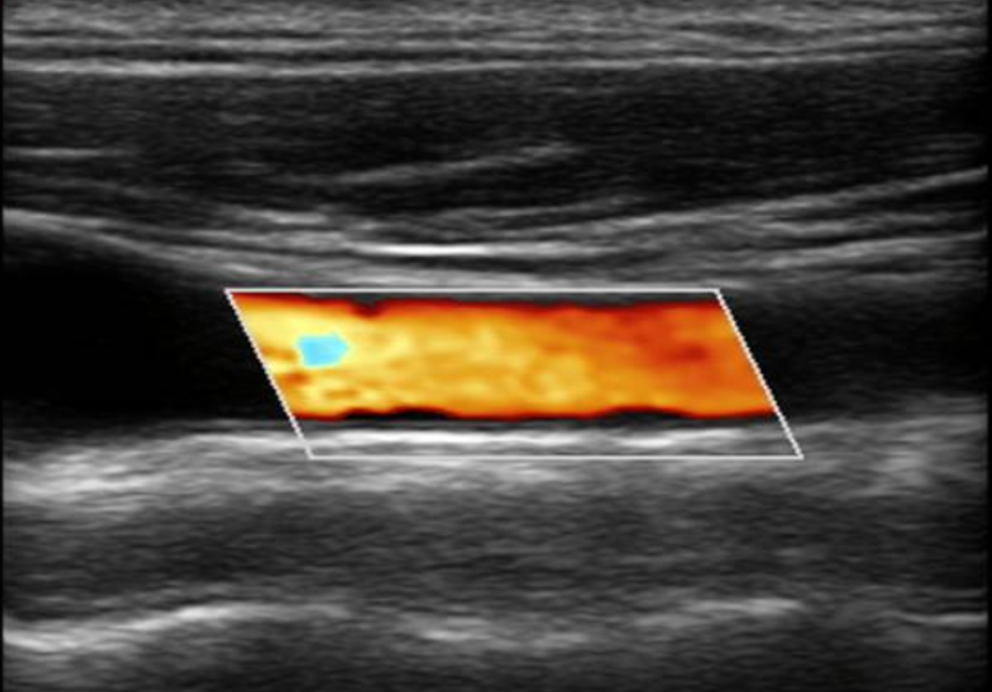

Deep Vein Thrombosis (DVT) 20 minutes

Whole body ultrasounds provide a non-invasive, painless, imaging option, allowing for the assessment of various organs without exposure to radiation.

This screening can help identify abnormalities such as tumors, cysts, or vascular issues at an early stage, potentially improving treatment outcomes. Our general screening exams include: breast, thyroid, kidneys, liver, spleen, aorta, pancreas, and calf veins.